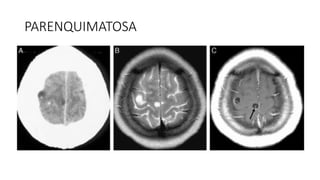

PARENQUIMATOSA

• #38 Cisticercos parenquimatosos. TC con contraste (A) y RM con secuencias potenciadas en T2 (B) y T1 con gadolinio en el plano transversal (C). Se ven peque˜nas lesiones quísticas corticales frontales derechas, con mínimo edema perilesional, realce anular y escólex visible en su interior (flecha